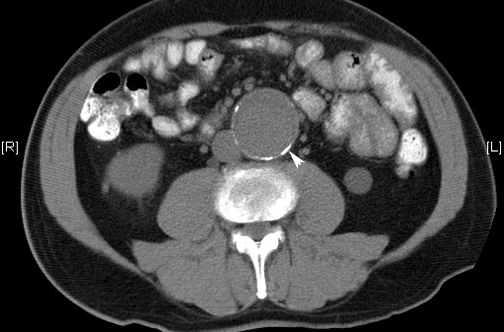

En un ensayo clínico realizado en Dinamarca se muestra el beneficio de rastrear en los varones de 65 a 74 años la presencia de aneurisma de aorta abdominal, enfermedad arterial periférica e hipertensión. The Lancet 28 de agosto de 2017